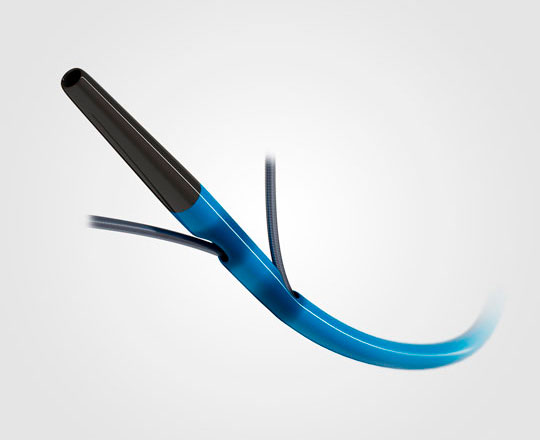

El dispositivo Conformal (Conformal Medical, Estados Unidos) está diseñado para adaptarse a la anatomía de la orejuela de cada paciente y disminuir la necesidad de ecografías transesofágicas y anestesia general durante el implante.

Tiene un esqueleto de nitinol con dos filas de 20 anclajes que se fijan a la pared de la orejuela, con un recubrimiento matricial de espuma en forma de tapón. En la parte superior de este, la expuesta al contacto sanguíneo, lleva un recubrimiento con tejido de politetrafluoroetileno expandido (ePTFE) que evita la trombosis del dispositivo1.